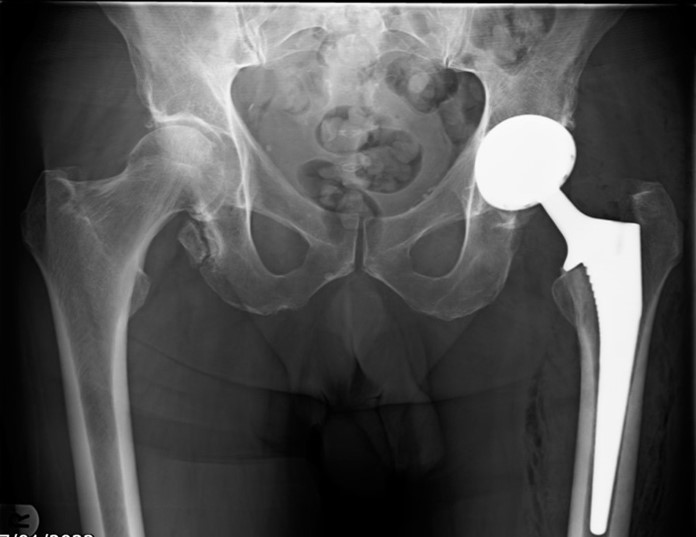

Total hip replacement through minimally invasive approach